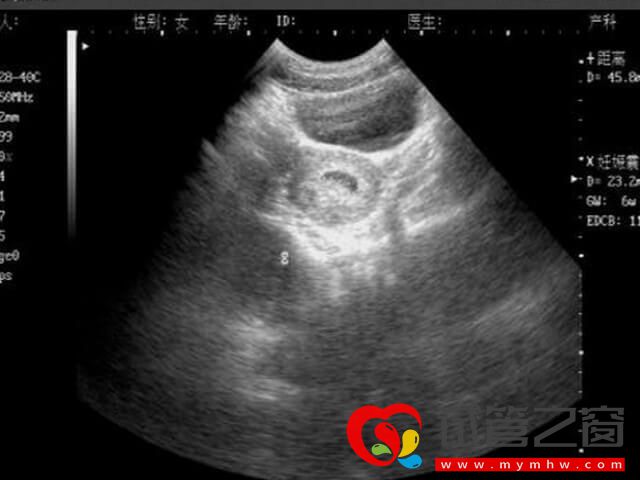

胎盘低指胎盘附着在子宫下段接近宫颈口位置,且胎盘边缘距子宫颈内口不足2㎝的情况,属于前置胎盘的一种。对于利用试管技术助孕的女女性来说,若是存在以下情况,就容易导致胎盘低置,反之就不容易出现: